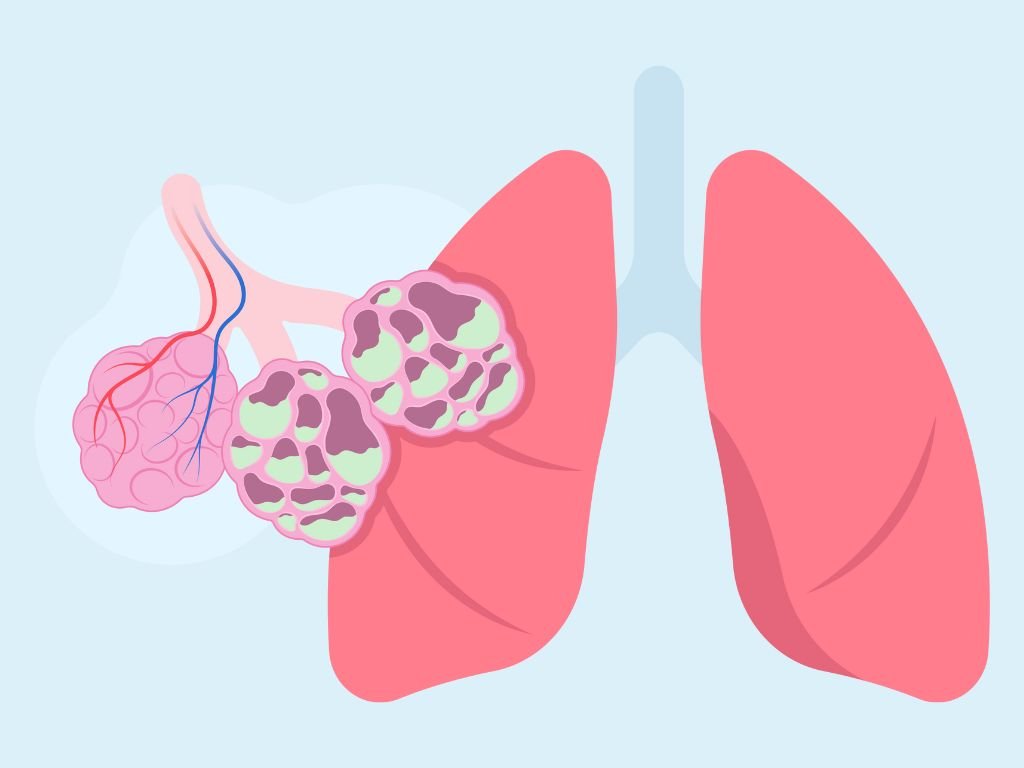

Rv Asthma & Lung Care Centre

Pulmonary Function Tests

Spirometry

DLCO